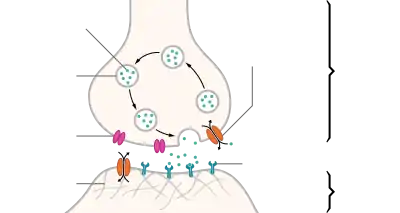

Mechanism and cycle

Synthesis

Storage

Neurotransmitters are generally stored in synaptic vesicles, clustered close to the cell membrane at the axon terminal of the presynaptic neuron. However, some neurotransmitters, like the metabolic gases carbon monoxide and nitric oxide, are synthesized and released immediately following an action potential without ever being stored in vesicles.[4]

Release

Generally, a neurotransmitter is released at the presynaptic terminal in response to an electrical signal called an action potential in the presynaptic neuron. However, low level 'baseline' release also occurs without electrical stimulation. Neurotransmitters are released into and diffuse across the synaptic cleft, where they bind to specific receptors on the membrane of the postsynaptic neuron.[5]

Receptor interaction

After being released into the synaptic cleft, neurotransmitters diffuse across the synapse where they are able to interact with receptors on the target cell. The effect of the neurotransmitter is dependent on the identity of the target cell's receptors present at the synapse. Depending on the receptor, binding of neurotransmitters may cause excitation, inhibition, or modulation of the postsynaptic neuron. See below for more information.

Elimination

In order to avoid continuous activation of receptors on the post-synaptic or target cell, neurotransmitters must be removed from the synaptic cleft.[6] Neurotransmitters are removed through one of three mechanisms:

- Reuptake – neurotransmitters are reabsorbed into the pre-synaptic neuron. Transporters, or membrane transport proteins, pump neurotransmitters from the synaptic cleft back into axon terminals (the presynaptic neuron) where they are stored for reuse.